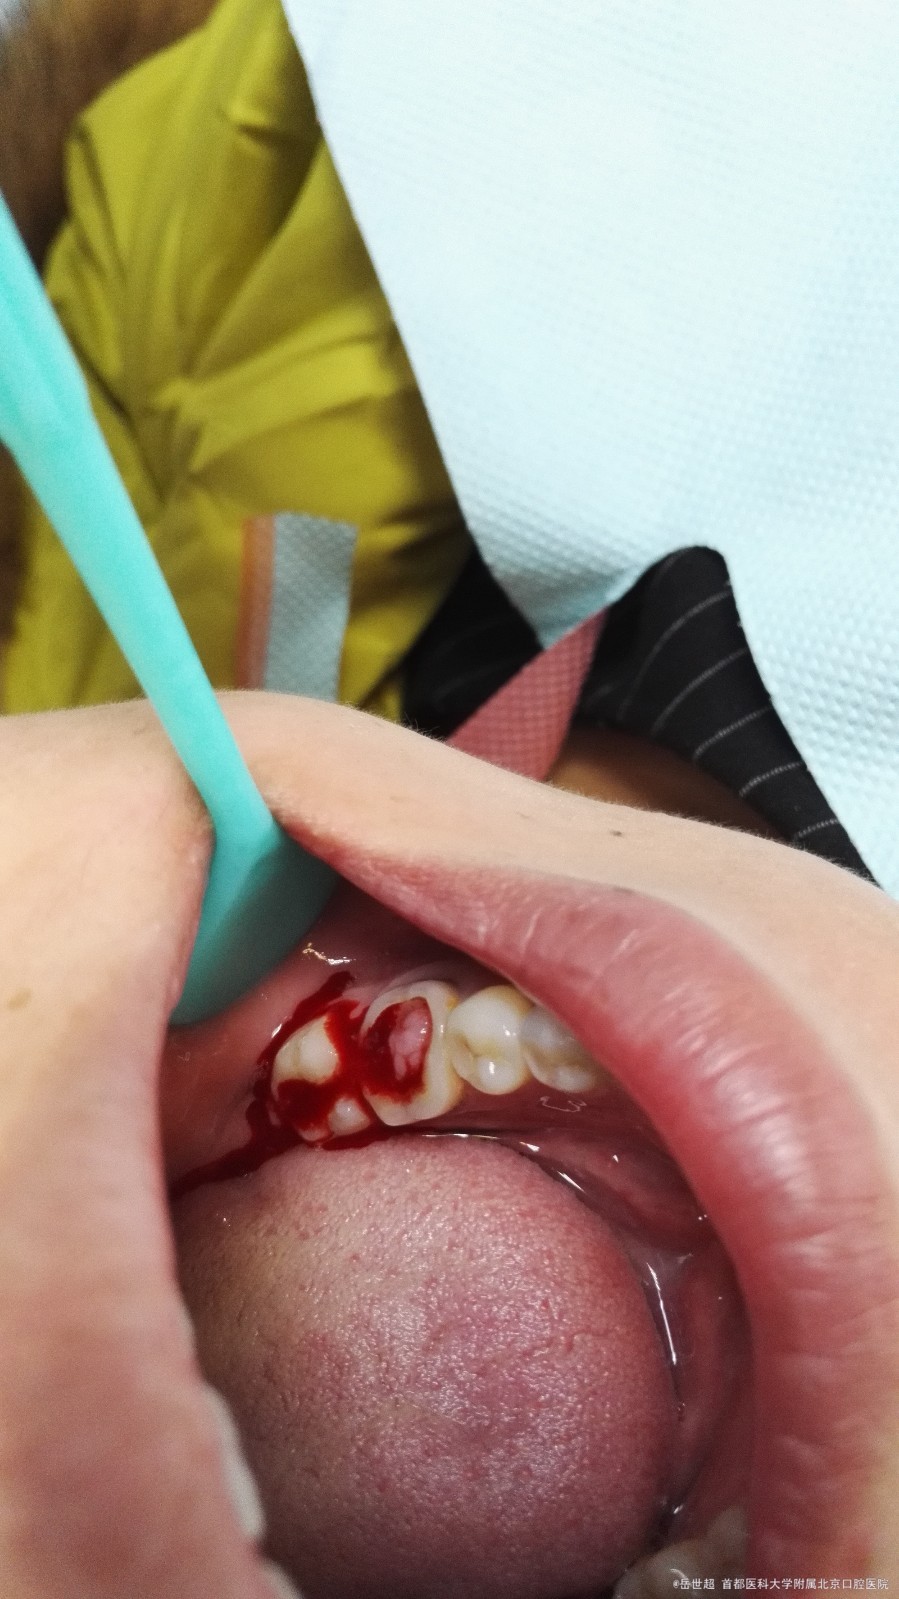

检查:左下6残冠,髓腔暴露,牙龈组织增生明显,充满开髓洞型,探及底穿,叩痛(—),

I°松动,牙龈缘轻度充血,根尖区无红肿,唇侧及前庭处未见窦道口。

患牙舌侧中央可探及10mm位点。

该例磨牙髓室底穿孔十分典型,具体症状是严重的牙髓息肉和根分叉处的炎症反应。